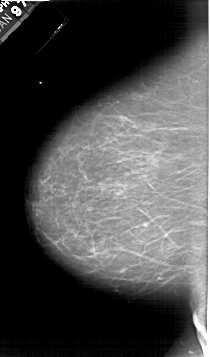

A_1615_1.LEFT_MLO

LEFT_MLO LINES 6541 PIXELS_PER_LINE 3706 BITS_PER_PIXEL 12 RESOLUTION 43.5 NON_OVERLAY